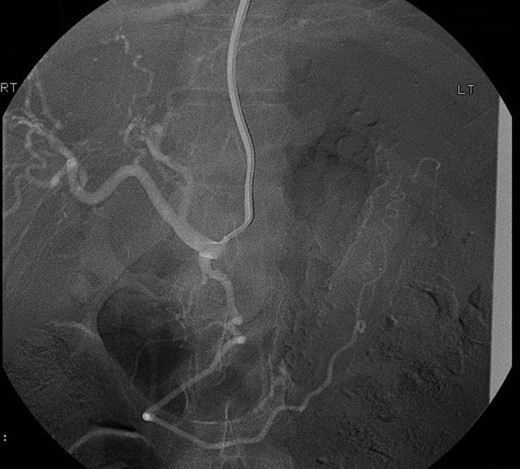

3D reconstruction images of the CTA revealed that the pseudoaneurysm was localized on an unnamed vessel branching directly from celiac trunk (Fig. 5). This deemed not suitable for endovascular embolization due to its size.

3D CTA reconstruction demonstrates the pseudoaneurysm (arrow) originating from the unnamed vessel.